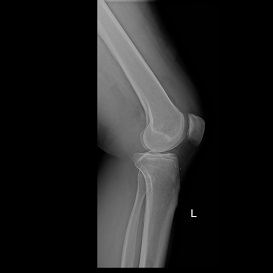

KNEE REPLACEMENT

As the knee ages it may come to a point where cartilage has eroded away to expose bone. Bone grinding on bone as a person is walking is very painful. Fortunately orthopaedic science has evolved to a solution whereby the knee can be replaced with a mechanical prosthesis.

Presently, the results are generally very good with excellent pain relief and mobility after the operation. Longevity of the prosthesis has improved to a point where the 10 year survival is more than 95% in some series.

As all surgery, the procedure is not entirely risk free. Deep venous thrombosis at 1% incidence and infection at 0.4% are most common complications, but stiffness, bleeding, nerve injury etc. can occur.

Below see the pre operative pictures of a normal knee, a diseased knee and a replaced knee.